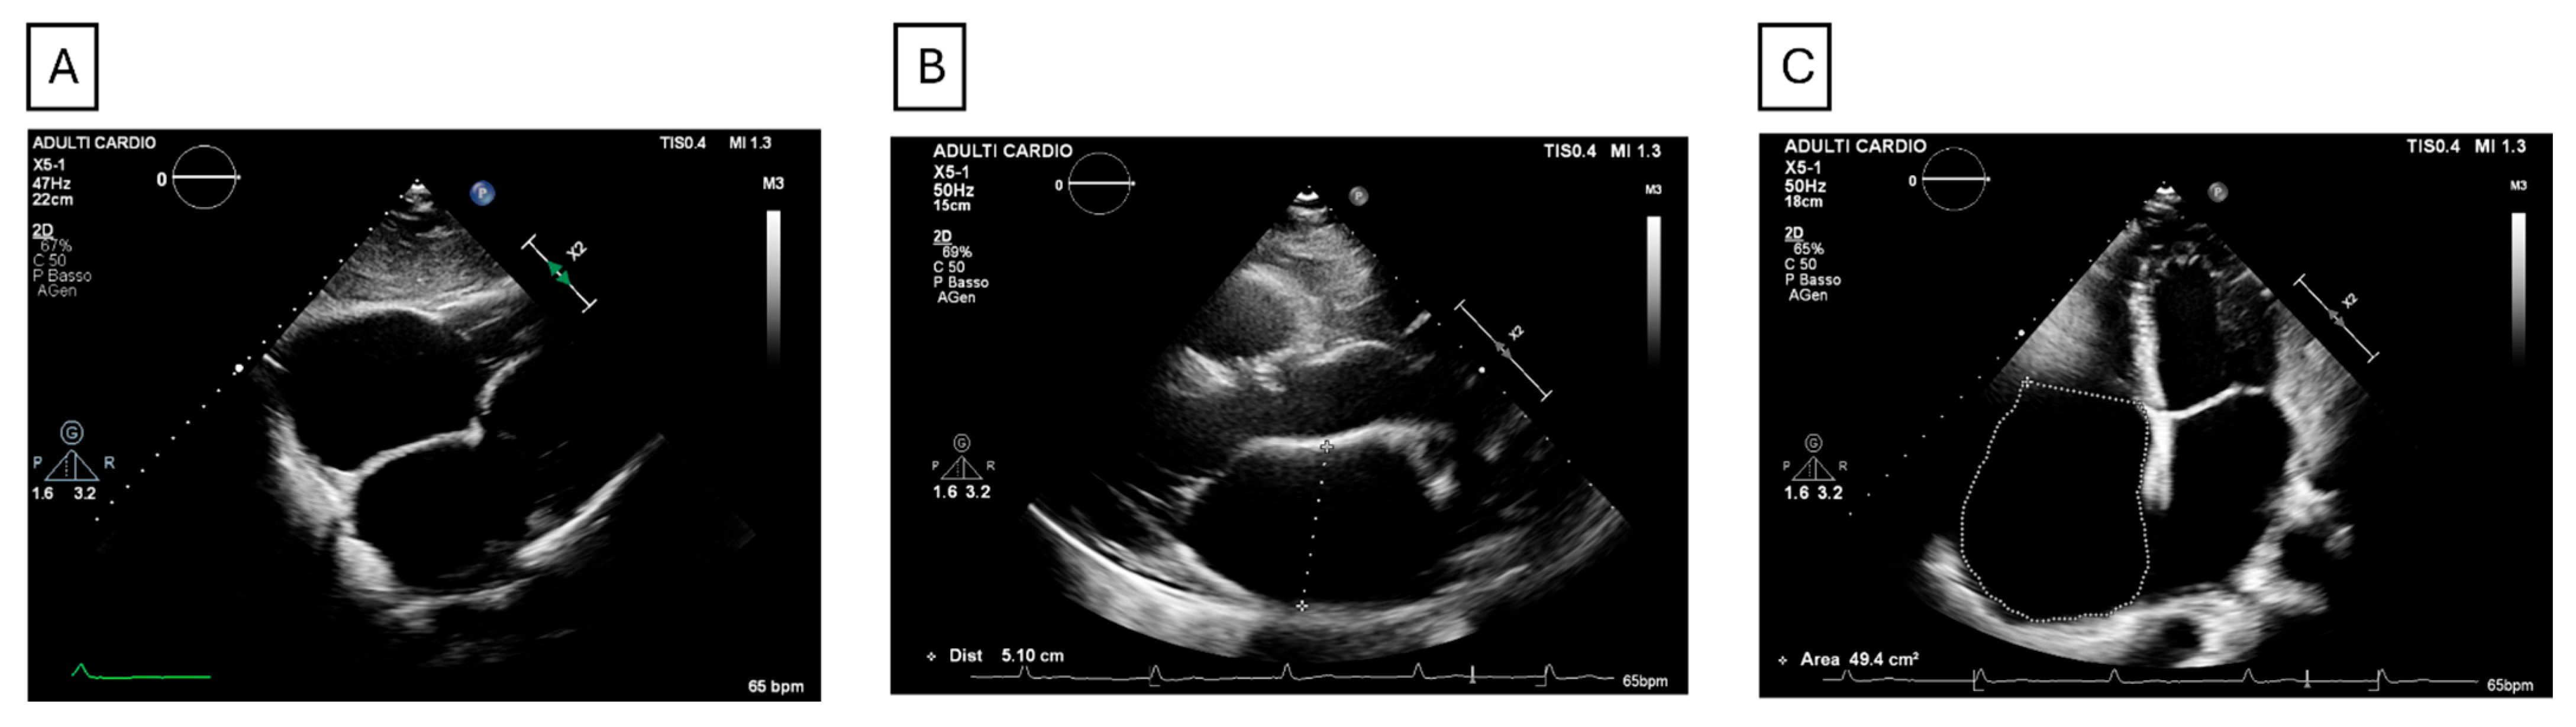

- Forleo, C.; Dicorato, M.M.; Carella, M.C.; Basile, P.; Dentamaro, I.; Santobuono, V.E.; Guaricci, A.I.; Resta, N.; Ciccone, M.M.; Arbustini, E. NPPA-Associated Atrial Dilated Cardiomyopathy: Genotypic and Phenotypic Insights From an Ultrarare Inherited Disorder. JACC Case Rep. 2025, 30, 105141. [Google Scholar] [CrossRef] [PubMed]